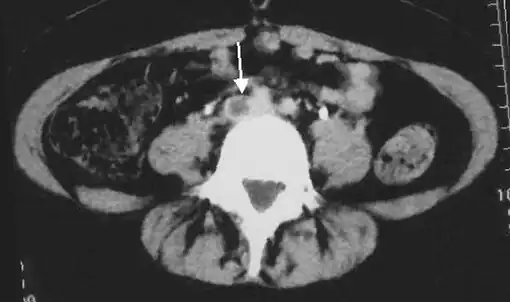

Doppler ultrasonography showing absence of flow and hyperechogenic content in a clotted femoral vein (labeled subsartorial[lower-alpha 8]) distal to the branching point of the deep femoral vein. When compared to this clot, clots that instead obstruct the common femoral vein (proximal to this branching point) cause more severe effects due to impacting a significantly larger portion of the leg.[122] An abdominal CT scan demonstrating an iliofemoral DVT, with the clot in the right common iliac vein of the pelvis

An abdominal CT scan demonstrating an iliofemoral DVT, with the clot in the right common iliac vein of the pelvis